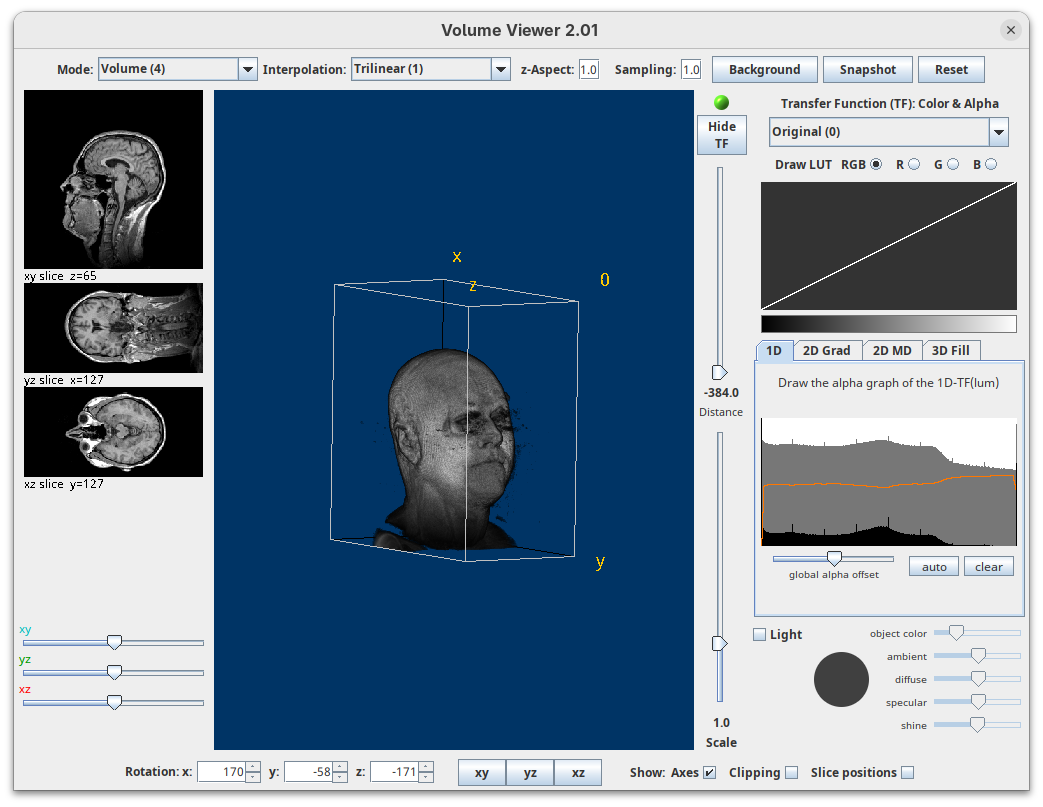

Volume Viewer

Volume Viewer is a more powerful plugin for 3D visualization as it supports slicing, projections, and rendering. The interface is interactive and intuitive to use. To open it:

- Go to

Plugins>Volume Viewer. The main interface will open in theSlicemode.

- Click around and move the sample to see optical sections from different angles.

- Then, activate the

Volumemode to render the sample’s surface in 3D and explore it as well, playing with the different rendering parameters.

Volume Viewer also provides a way to take snapshots of the current view.